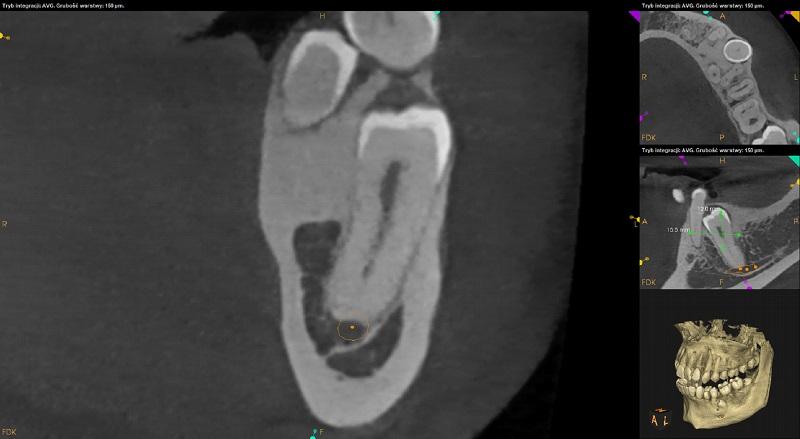

Ząb 38 – częściowo zatrzymany. Położony poziomo, koroną skierowany w stronę mezialną. Wierzchołki korzeni zagięte. Kanał nerwu zębodołowego dolnego biegnie po stronie językowej potem poniżej zęba 38. Korzenie w kontakcie z kanałem. Poziom wyrostka po stronie dystalnej zęba 37 obniżony.